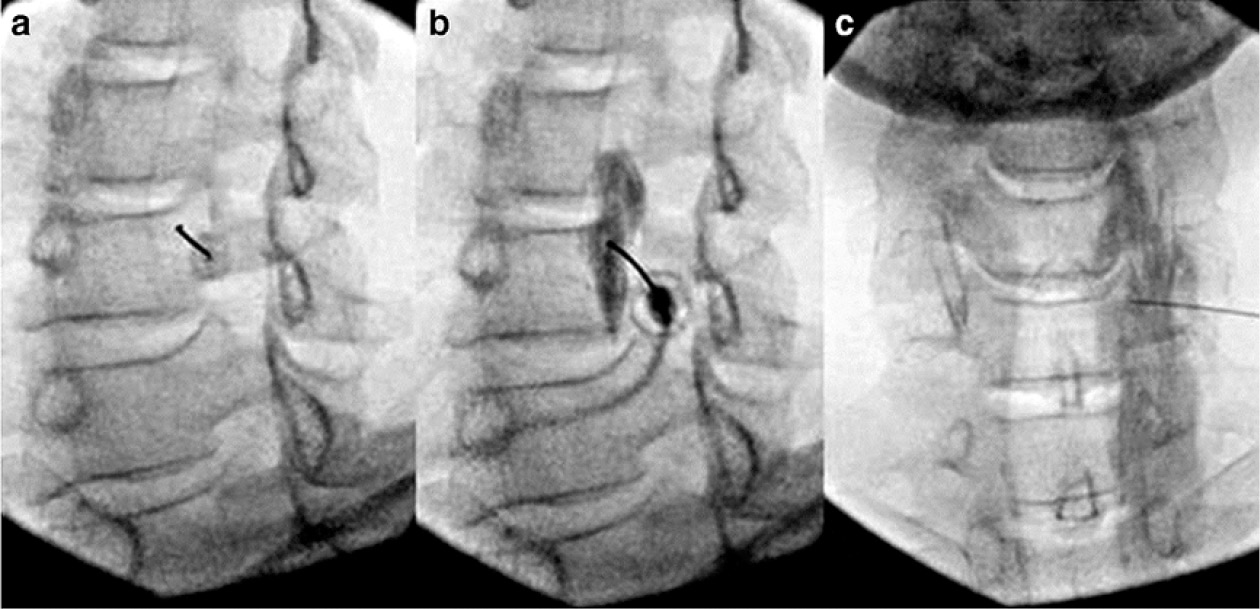

Ультрасонография (УЗИ) позволяет визуализировать ключевые структуры мягких тканей, которые дают возможность точно разместить иглу для блокады. Анатомическими ориентирами для блокады звёздчатого ганглия являются сонная артерия, длинная мышца шеи и передний бугорок шестого позвонка (бугорок Шассиньяка) [50]. В отличие от флюороскопического доступа (рис. 2), конечной точкой УЗ-доступа не является контакт с костью. Целью является плоскость между латеральной частью длинной мышцы шеи сзади и предпозвоночной фасцией, покрывающей заднюю часть оболочки сонной артерии спереди. Существуют явные различия между конечными точками иглы при флюороскопическом и УЗ-доступе, который разделён длинной мышцей шеи. УЗ-подход нацелен на переднюю поверхность мышцы (рис. 3), тогда как рентгеноскопический подход нацелен на заднюю поверхность мышцы. Кроме того, прямая визуализация сосудов и мягких тканей сводит к минимуму риск случайного укола иглой и последующей травмы при ультразвуковом контроле. Дополнительным преимуществом использования УЗИ является то, что требуется меньший объём инъекции для создания той же степени блокады, что сводит к минимуму любые необоснованные побочные эффекты введения местных анестетиков [51]. В целом под контролем УЗИ используется около 3 мл по сравнению с более чем 5 мл при рентгеноскопическом доступе.

Рис. 2. Блокада звёздчатого ганглия под рентгеноскопическим контролем: а) косая проекция: игла касается кости на уровне С6 в месте соединения крючковидного отростка и тела позвонка; b) изображение, показывающее внесосудистое, внеинтратекальное распространение контраста; c) вид после введения местного анестетика [48] / Fig. 2. Blockade of the stellate ganglion under fluoroscopic control: a) oblique projection: the needle touches the bone at the C6 level at the junction of the uncinate process and the vertebral body; b) image showing extravascular, extra-intrathecal spread of contrast; c) view after administration of local anesthetic [48]